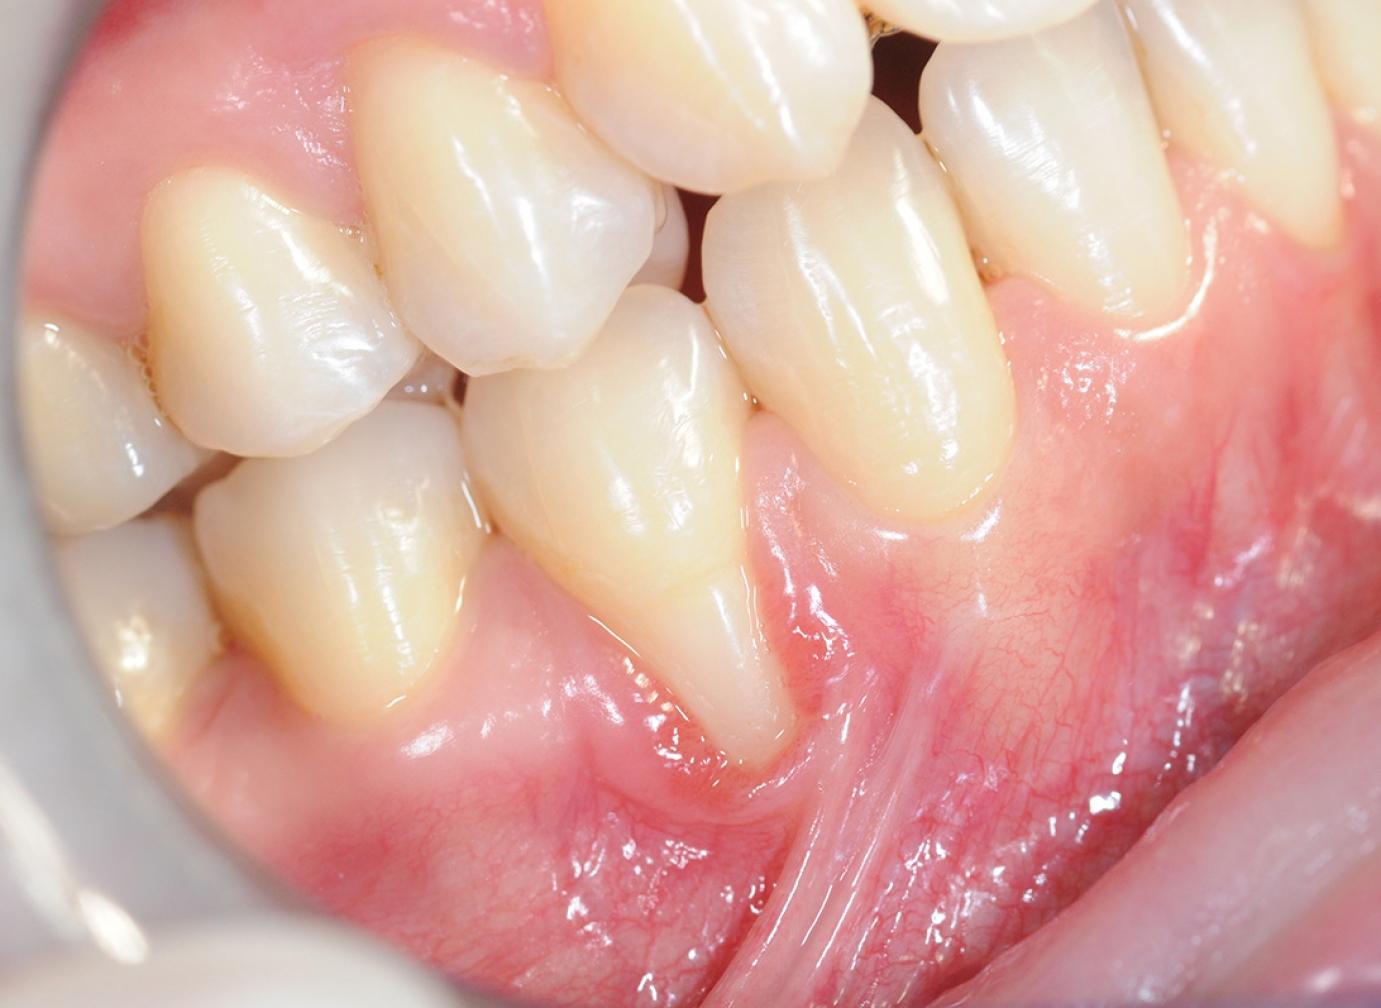

Az ínyrecesszió az ínyvisszahúzódás fogorvosok által használt elnevezése. Lehet körkörös, mely szinte mindig fogágybetegséghez társul, de lehet egyoldali is, tehát vagy csak a fog külső, vagy csak a belső oldalán jelentkező. Az egyoldali ínyrecessziók általában nem járnak a fogak meglazulásával vagy elvesztésével, mert csak ritkán kapcsolódik hozzájuk fogágybetegség, illetve csontpusztulás. Ezen esetek nagy részében lehetőség van parodontológus szakorvos bevonásával visszaállítani az eredeti állapotot. Fontos tudni, hogy fogszabályozás alatt vagy után is kialakulhat egyoldali ínyrecesszió akár a fogak külső, akár belső oldalán. Jellemzően súlyos torlódások vagy Angle II-es eltérések megoldása után jelentkezik az alsó metszők külső oldalán. Esetleg foghúzással kombinált rögzített készülékes kezeléseknél abban az esetben, ha a fogszabályozás után a metszőfogak erősen befelé dőlnek.